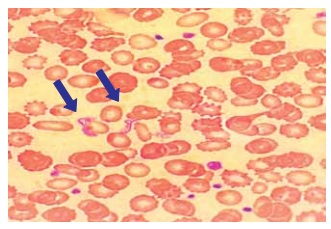

A figura a seguir apresenta um esfregaço de sangue

venoso, em que são visíveis formas características de

um protozoário flagelado. Esse parasita é transmitido por

insetos triatomíneos e está associado a uma doença tropical de grande impacto na América Latina.